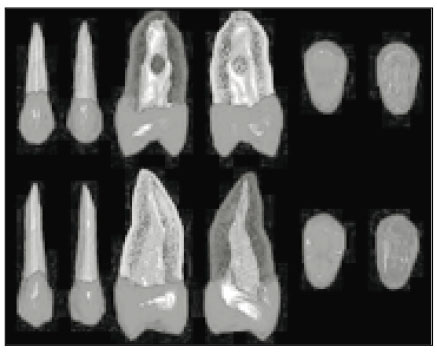

Fig. 5

Three-dimensionally reconstructed lower premolars. Upper: 1st premolar, Lower: 2nd premolar. From left to right: labial, lingual, mesial, distal, incisal, apical view